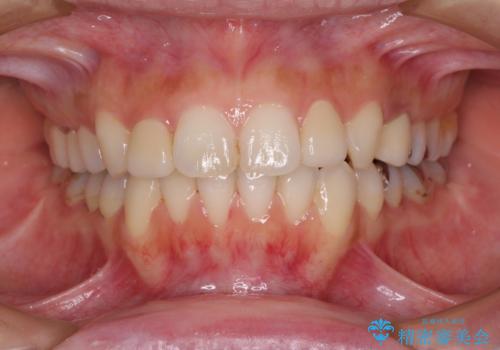

- 前歯のデコボコを気にして来院された患者様です。

上顎右側犬歯が八重歯になっており、それによって奥歯が前方に移動しているため、右側の咬み合わせの改善が必要と判断されました。

マウスピース矯正では改善に時間がかかる、あるいは改善しきれない可能性があることを伝えたところ、短期間で確実に治療ができるワイヤー矯正を選択されました。

より治療を速やかに行うため、上顎右側にアンカースクリューを使用し、目標としていた1年半ほどで治療を終えることができました。